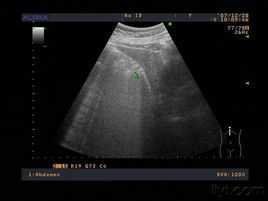

萎縮性膽囊炎病人常反覆發作右上腹疼痛,平時也隱隱作痛,並有胃納差、噯氣、腹脹等消化道症狀。B超檢查見膽囊體積很小,直徑不超過3—4厘米,壁厚,無收縮功能,口服膽囊造影劑檢查時,膽囊多不能顯影。